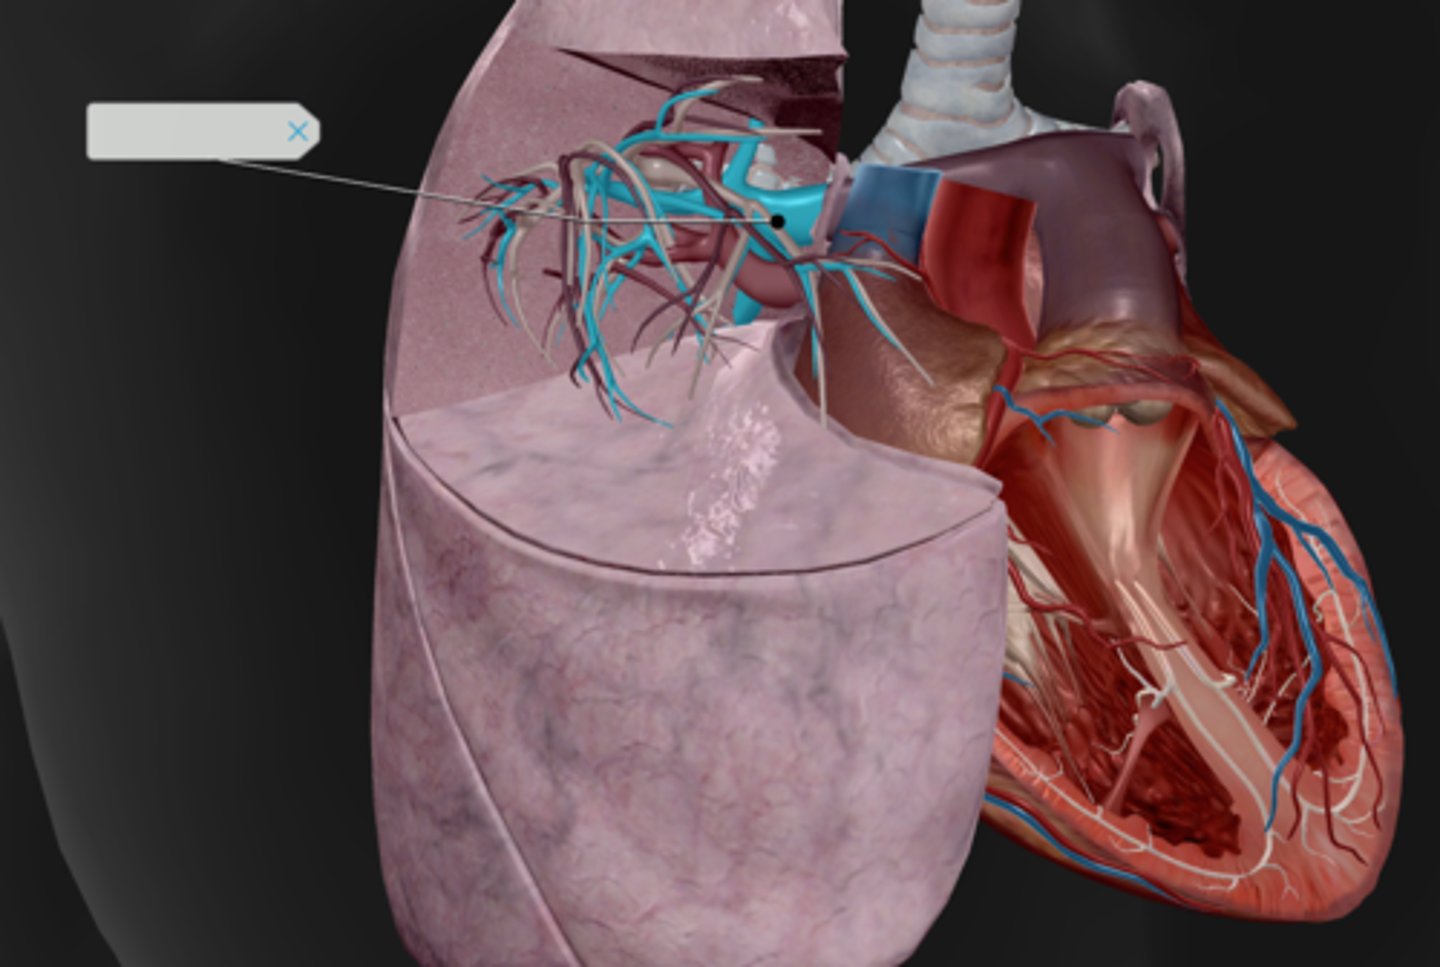

Hilum

Pulmonary arteries

Pulmonary veins

Pulmonary trunk

Diaphragm